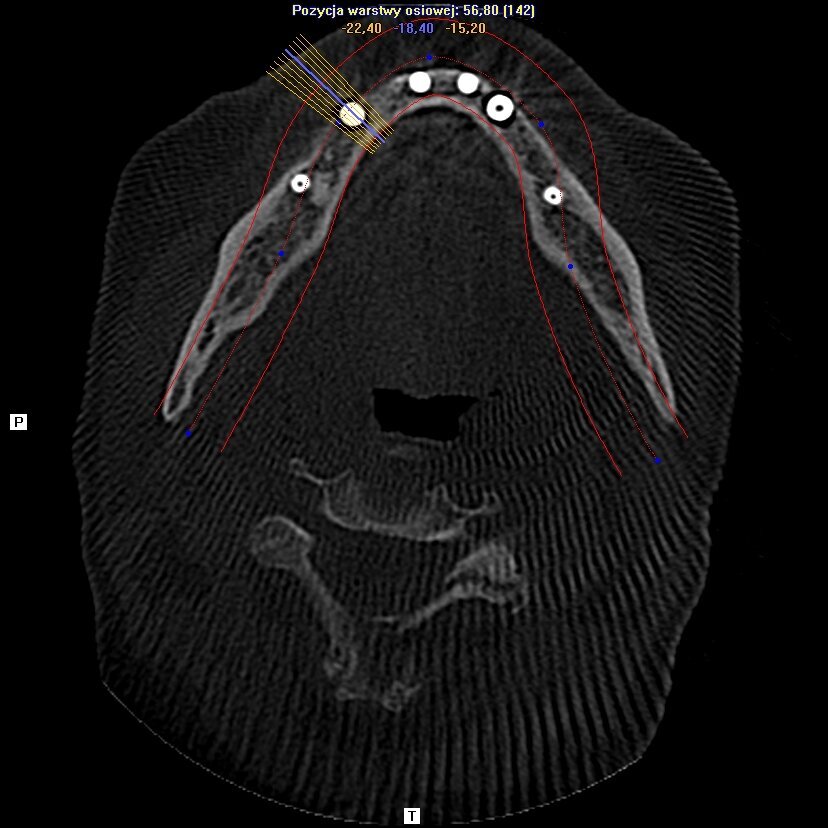

Wykonanie badania tomograficznego potwierdziło diagnozę o zaawansowanej nierokującej chorobie przyzębia (Ryc. 2). Po konsultacji została podjęta decyzja o ekstrakcji wszystkich zębów w żuchwie, natychmiastowym wprowadzeniu implantów z jednoczesną czasową odbudową protetyczna stałą mocowaną na wszczepionych implantach. Zlecono rutynowe badanie lekarskie i laboratoryjne.

Implanty zostały wprowadzone wg zasady przylegania w cieniu, tzn. wszczep musi na całej swojej długości mieć kontakt z którąś ze ścian zębodołu 1-2 mm subkrestalnie (Ryc. 4). W przypadku konieczności użycia membrany, musi ona mieć możliwość rozpostarcia się nad ubytkiem kostnym i implantem tak, aby odległość pomiędzy membraną a wszczepem nie była mniejsza niż 2 m (Ryc. 3). Wszczepy o

przygotowanej wcześniej protezie czasowej metodą bezpośrednią. Czasowe uzupełnienie protetyczne osadzono, używając cementu tymczasowego (Ryc. 5 i 6). Zlecono wykonanie zdjęcia techniką CBCT (Ryc. 7). Wizytę kontrolną wyznaczono następnego dnia, a szwy zostały usunięte po 10 dniach.

zlecono też wykonanie kontrolnego zdjęcia CBCT i następnego po 12 miesiącach (Ryc. 10 i 11).

W kwietniu 2017 r. został wykonany status periodontologiczny pozostałego uzębienia i wszczepionych implantów (Ryc. 12) i ponowne badanie CBCT (Ryc. 13- 15). Stan 3 lata po zabiegu przedstawiono na rycinach 16-18. Pacjentka jest ujęta w programie Recall w cyklu 6-miesięcznym od dnia wykonania zabiegu.